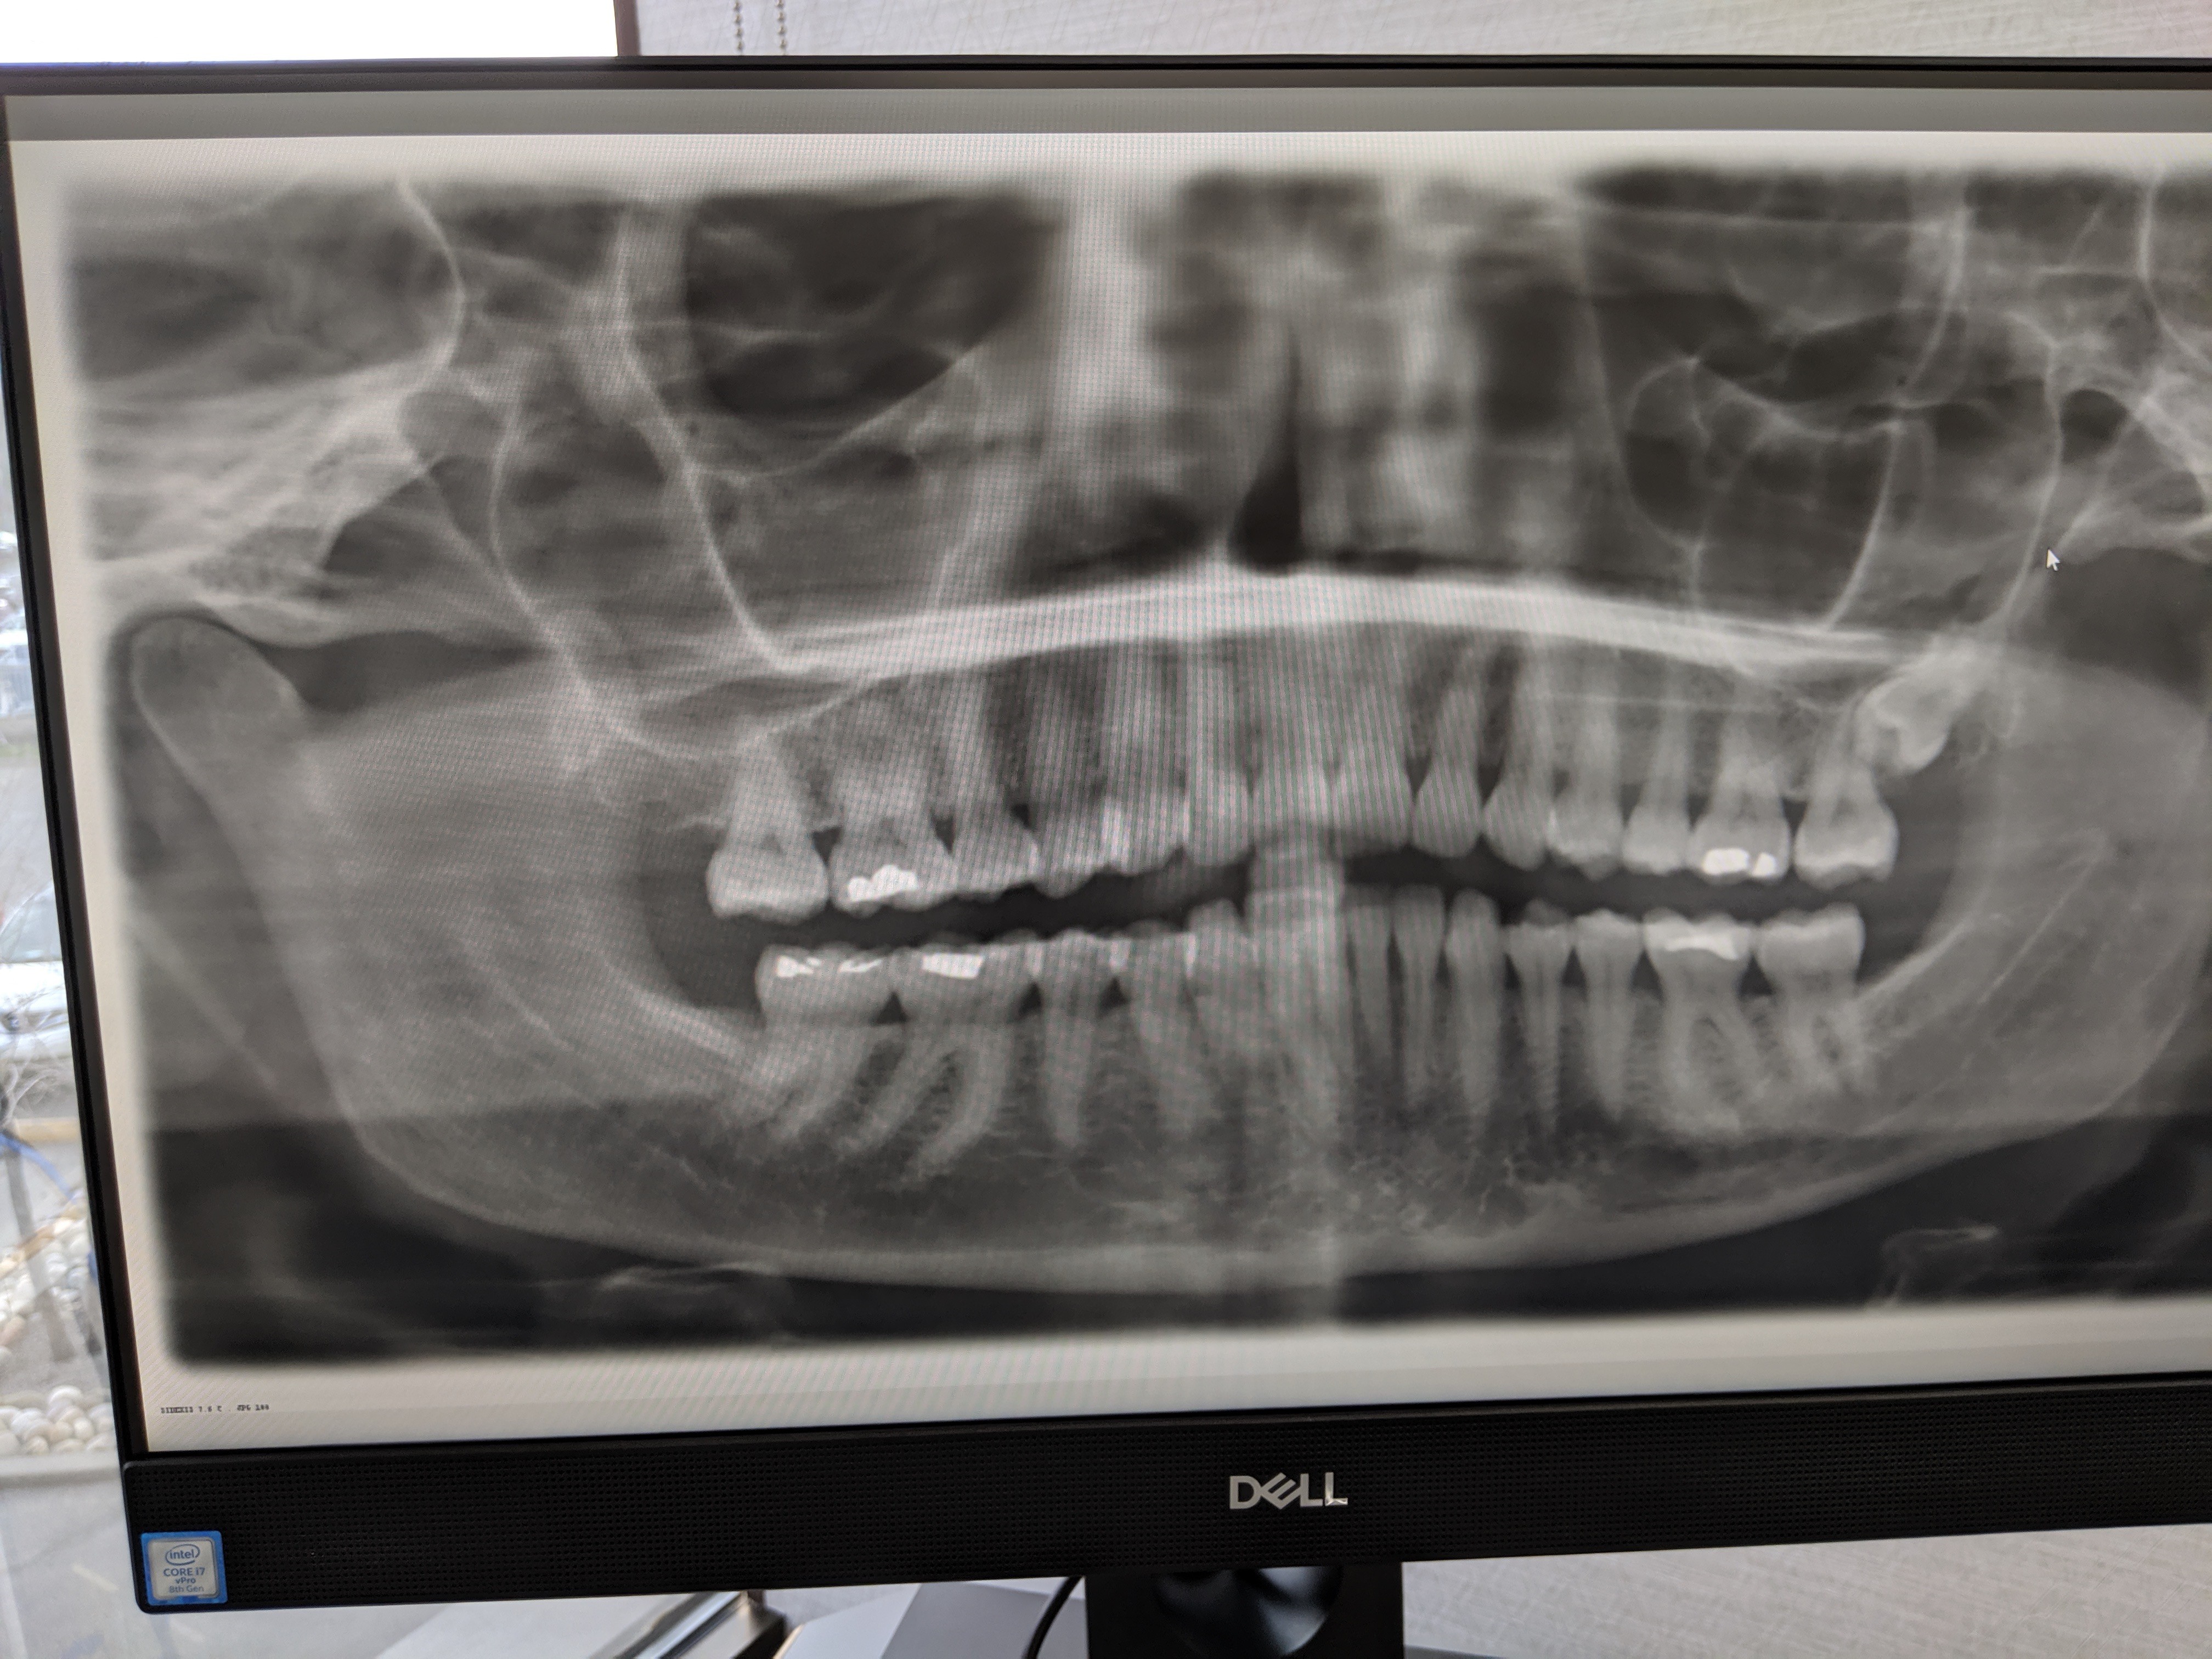

Imagine go to Cochrane Dental and paying for X-rays, it shows a severely impacted wisdom tooth, then a second time and the Dentist Dr Sawka told the courts that he decided to leave a lying dog lie. In other words, not tell you and let you suffer, as my wife did for over 10 years. Chronic mouth infections that were so serious she was in urgent care on many occasions GI Infections, gastrointestinal infections followed, extremely high blood pressure, calcification of the styloid ligaments. And Dr. Sawka's expert Dr. Maclean agr... read more